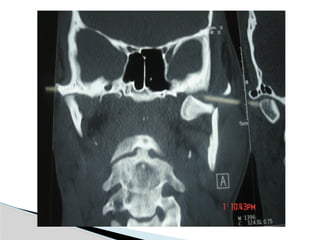

CT

Significant displacement or dislocation,

mechanical obstruction, mult trauma pt, &

intracapsular fracture.

Conventional Radiology At least2 views at right angle to each other. Mandibular series: PA, Lateral oblique or panoramic, & Towne’s view (projects condyle below mastoid process). CT Significant displacement or dislocation, mechanical obstruction, mult trauma pt, & intracapsular fracture. MRI St injuries: effusion, visualization of disc. Imaging